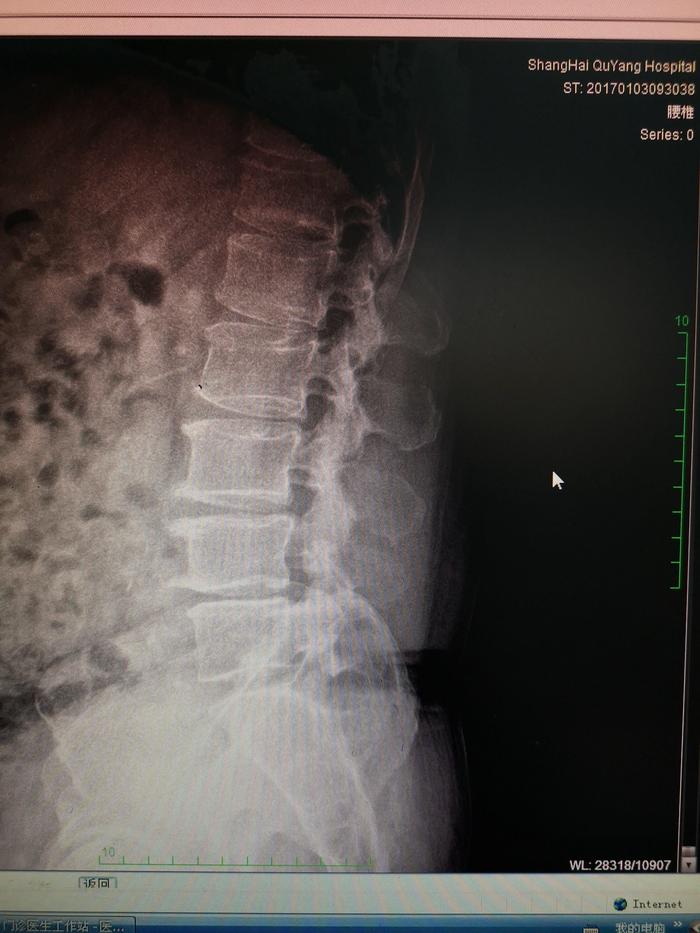

下面的是一位腰间盘手术后进行内固定治疗,术后1年的患者的X光片子。

我们可以对照一下手术前和手术之后我标记的部位的关节的改变

治疗前的脊柱

开x光片上,我们可以看到治疗前腰4-5椎体间关节是病变不明显的,那么治疗之后椎体间出现了间隙变窄,硬化,增生加重,而脊柱侧弯骨盆旋移都没有得到纠正。术后不到1年再次出现腰痛,不能背伸,也不能侧弯。